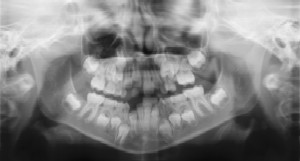

Dental Radiographs (X-Rays)

Radiographs (X-Rays) are a vital and necessary part of your child’s dental diagnostic process. Without them, certain dental conditions can and will be missed.

Radiographs detect much more than cavities. For example, radiographs

may be needed to survey erupting teeth, diagnose bone diseases, evaluate

the results of an injury, or plan orthodontic treatment. Radiographs

allow dentists to diagnose and treat health conditions that cannot be

detected during a clinical examination. If dental problems are found and

treated early, dental care is more comfortable for your child and more

affordable for you.

The American Academy of Pediatric Dentistry recommends radiographs and examinations every six months for children with a high risk of tooth decay. On average, most pediatric dentists request radiographs approximately once a year. Approximately every 3 years, it is a good idea to obtain a complete set of radiographs, either a panoramic and bitewings or periapicals and bitewings.

Pediatric dentists are particularly careful to minimize the exposure of their patients to radiation. With contemporary safeguards, the amount of radiation received in a dental X-ray examination is extremely small. The risk is negligible. In fact, the dental radiographs represent a far smaller risk than an undetected and untreated dental problem. Lead body aprons and shields will protect your child. Today’s equipment filters out unnecessary x-rays and restricts the x-ray beam to the area of interest. High-speed film and proper shielding assure that your child receives a minimal amount of radiation exposure.